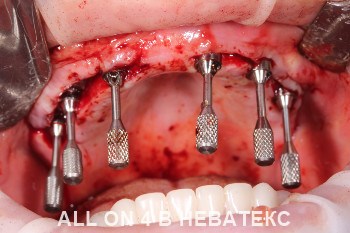

All-on-4 в клинике НЕВАТЕКС.МОСКВА

- Операция

Установка имплантов по протоколу All-on-4. По показаниям, возможна установка имплантов малоинвазивным способом БЕСКРОВНО с помощью прокола лазерным скальпелем. Создается опора для протеза и его винтовой фиксации.

Во время операции